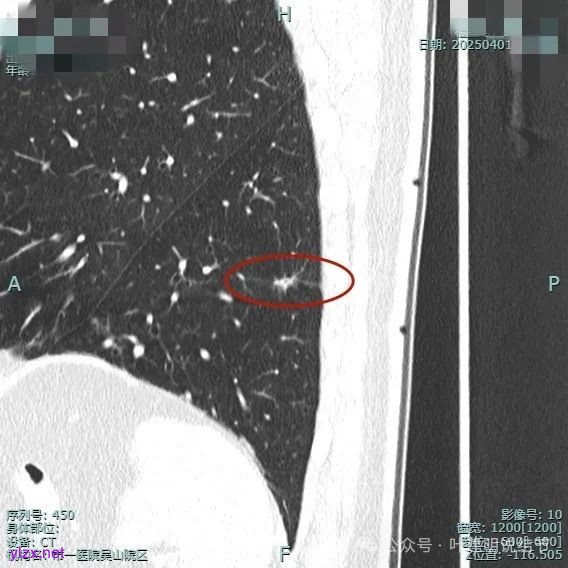

我们把三次薄层的放在一起看看:

这个结节虽然仍在,或许也有人觉得密度减低也不是太明显,但我想至少随访长达1年是没有明显进展的,而且虽有毛刺但显得过长;虽有空泡但显得更像细支气管扩张;虽有灶内密度杂乱但更显得像慢性炎的杂乱;虽有血管进入但显得异常增粗是不明显的;虽表面不平但整体缺乏收缩力,也无膨胀感。所以总体上更符合慢性炎些,至少是能随访的。此例之所以当时就觉得像炎性些,最关键的也不是上面讲的这几点,而是横断面看圆形或类圆形且有相应恶性影像特征,但纵向是偏长条的,再加上上述影像特征有却不是典型恶性的毛刺、空泡与血管征等,所以才倾向炎性的考虑。我想最终的结果仍是要病理依据,但我们从风险高低以及前后对比综合评估应该是不变的原则与最接近真相的。